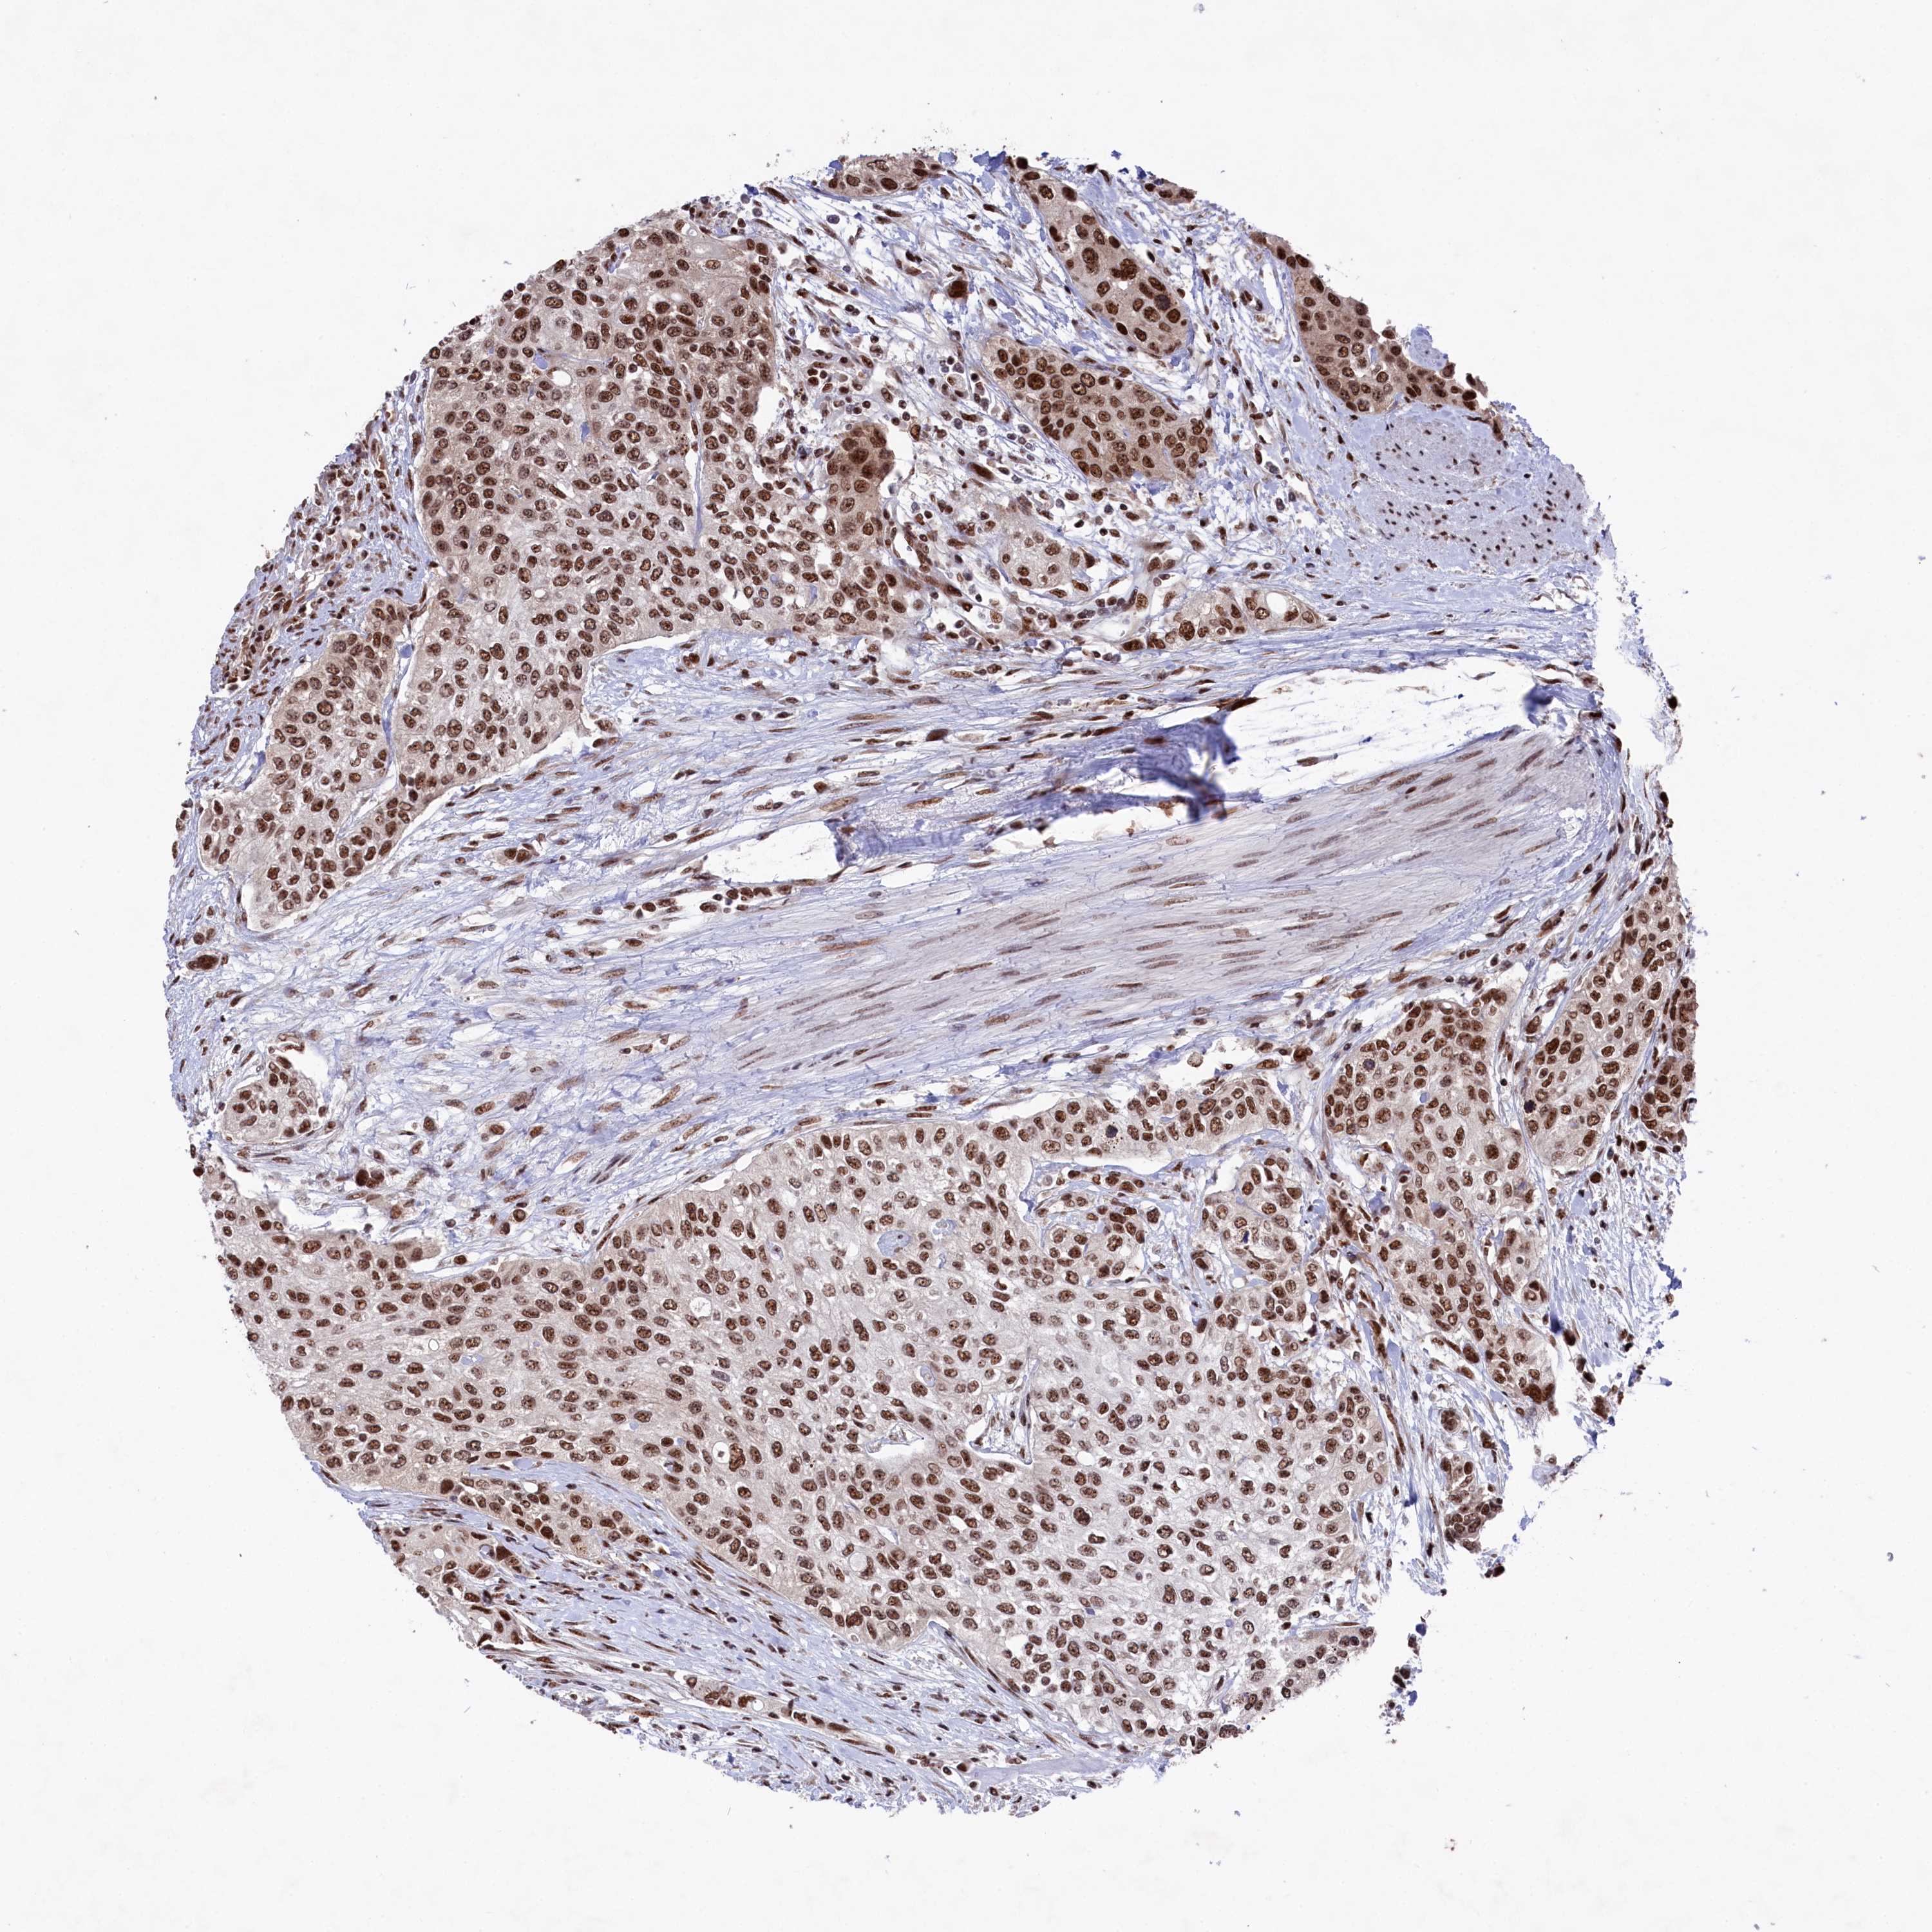

UROTHELIAL CANCER - Protein expressioni

A mouse-over function shows sample information and annotation data. Click on an image to view it in a full screen mode. Samples can be filtered based on level of antibody staining by selecting one or several of the following categories: high, medium, low and not detected. The assay and annotation is described here.

Note that samples used for immunohistochemistry by the Human Protein Atlas do not correspond to samples in the TCGA dataset.

Antibody stainingi

Antibody staining in the annotated cell types in the current human tissue is reported as not detected, low, medium, or high, based on conventional immunohistochemistry profiling in selected tissues. This score is based on the combination of the staining intensity and fraction of stained cells.

Each image is clickable and will lead to virtual microscopy that enables deeper exploration of all samples and also displays staining intensity scores, fraction scores and subcellular localization as well as patient and tissue information for each sample.

Antibody HPA041939

Staining

High

Medium

Low

Not detected

Intensity

Strong

Moderate

Weak

Negative

Quantity

>75%

75%-25%

<25%

None

Location

Nuclear

Cytoplasmic/membranous

Cytoplasmic/membranous,nuclear

Urothelial carcinoma, High grade

Urothelial carcinoma, Low grade

Urothelial carcinoma, NOS